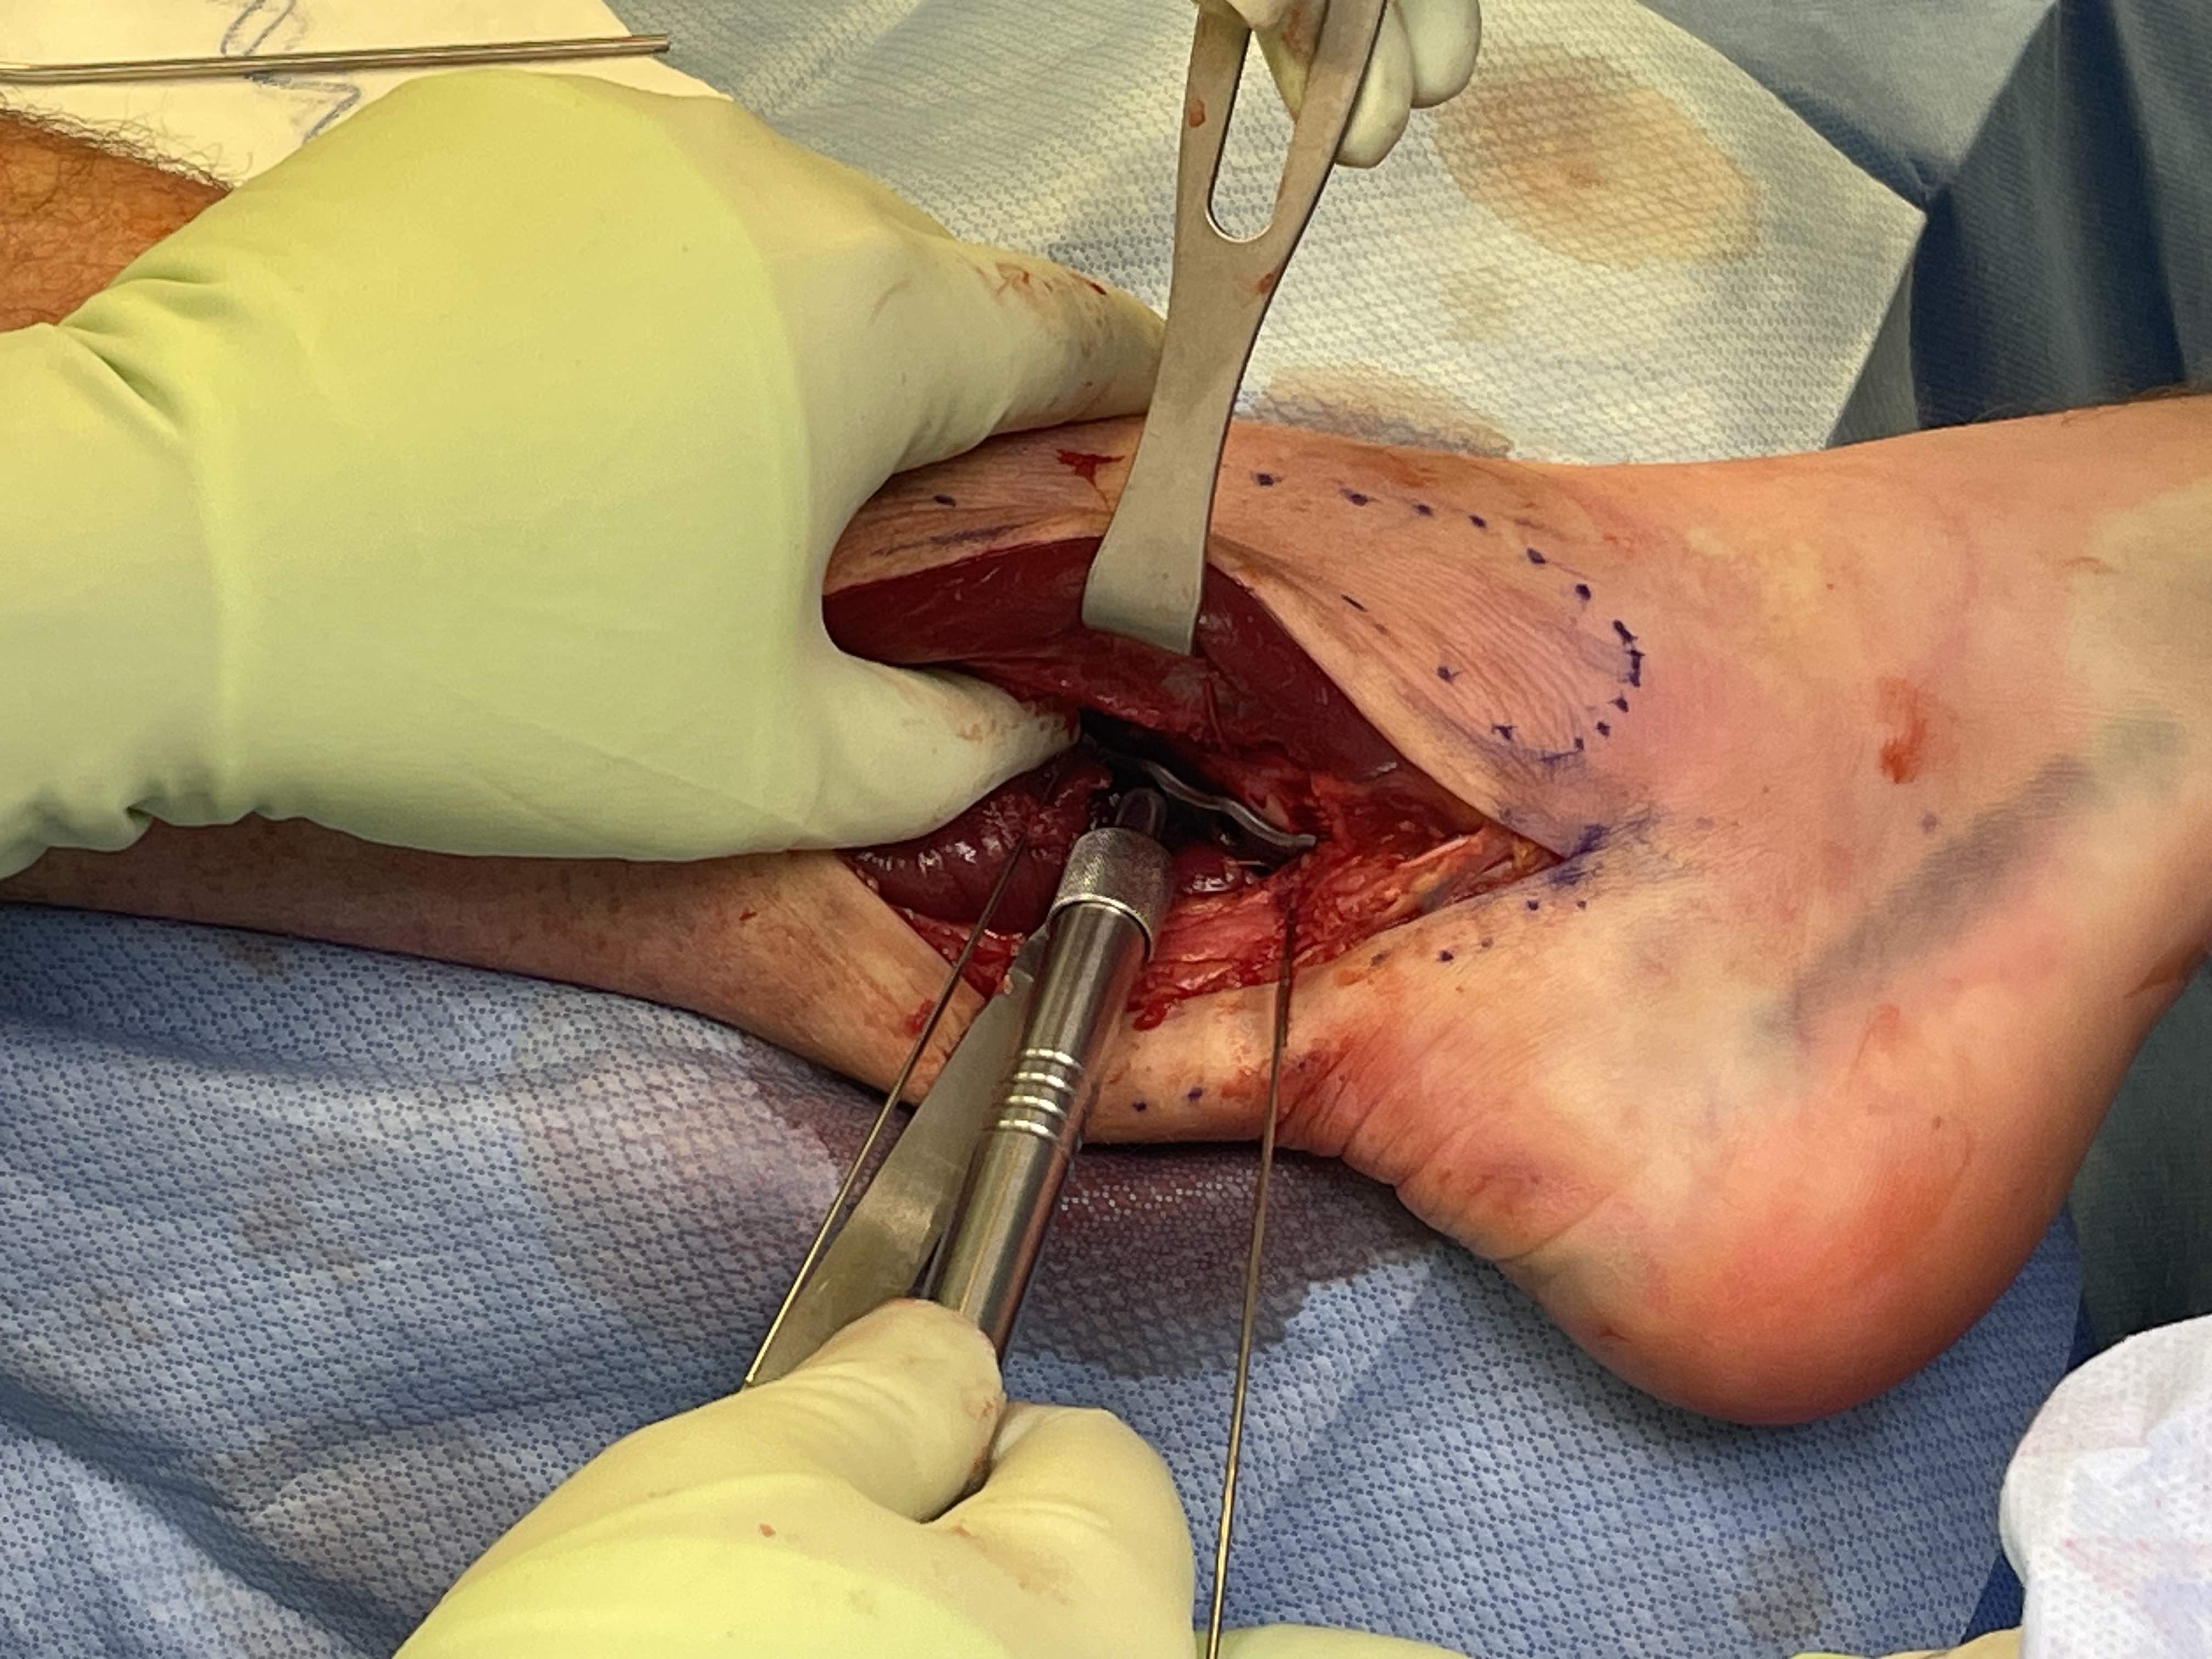

Posterolateral approach

Incision between tendoachilles and fibular

- divide investing fascia

- protect sural nerve / reflect posterior

Posterior tibia

- reflect peroneal tendons anterior

- divide fascia over FHL - reflect medial

- peroneal artery is proximal on interosseous membrane deep to peroneals

Fibular

- reflect peroneals posteriorly